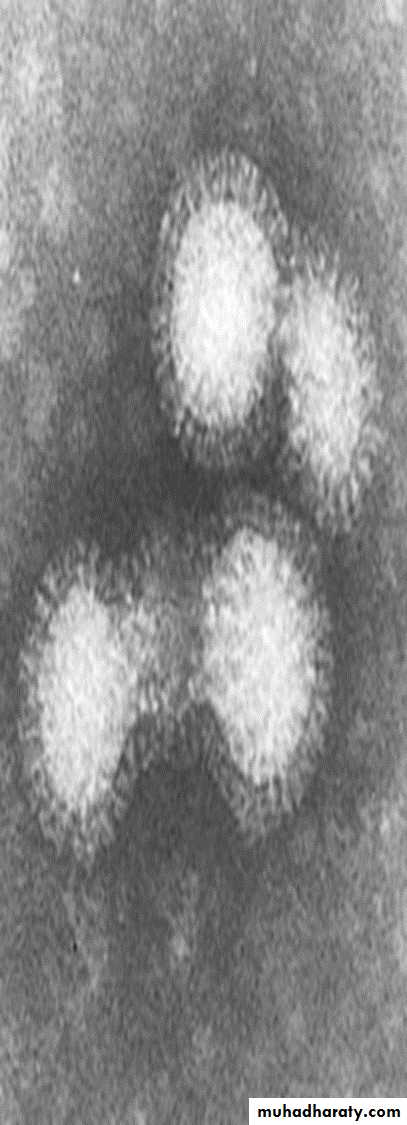

Influenza viruses are RNA viruses in the family Orthomyxoviridae that can affect birds and mammals including humans. They have surface projections are molecules of hemagglutinin and neuraminidase.